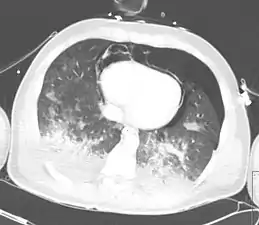

تصوير صدري مقطعي محوسب يُظهر تدمي صدري مع رضوضٍ رئوية شديدة